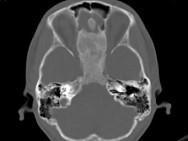

问题 女,17岁,鼻阻塞、头痛两年.如图所示符合筛骨病变最可能的诊断是()

选项 A.成骨肉瘤骨 B.纤维异常增殖症 C.软骨瘤 D.骨瘤 E.骨化性纤维瘤

答案 E